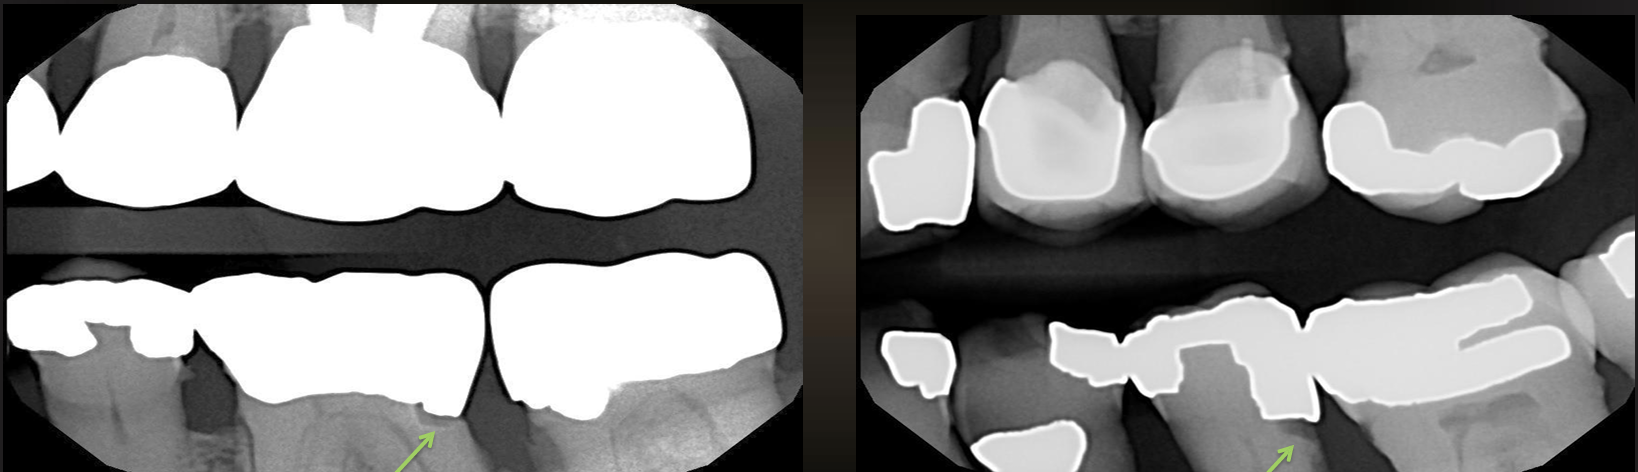

rampant caries

affects almost all teeth- usually caused by radiation

root surface caries

cratering on the roots of the teeth, involving cementum

buccal/lingual/proximal

saucer like radiolucency

may be confused with cervical burnout

can you have root surface caries without exposed roots?

no!

what are the arrows pointing to?

what are diagnostic confounders?

pits and fissures, cervical burnout, mach band effect, dental anomalies like hypoplastic pits and concavities produced by wear

mach band effect

an optical illusion where the human eye perceives faint light and dark bands at the boundary of two shades of gray, even if the transition is gradual

what is shown in the non-restored premolar?

mach band effect- the faint dark line under enamel is not caries, it is an ~optical illusion~

if you change angulation of radiograph or CBCT it would disappear

cervical burnout

apparent radiolucency below the CEJ due to anatomy or a gap between the enamel and bone covering the rooth

no root caries unless there is alveolar bone loss

what is the arrow pointing to?

hypoplastic pit